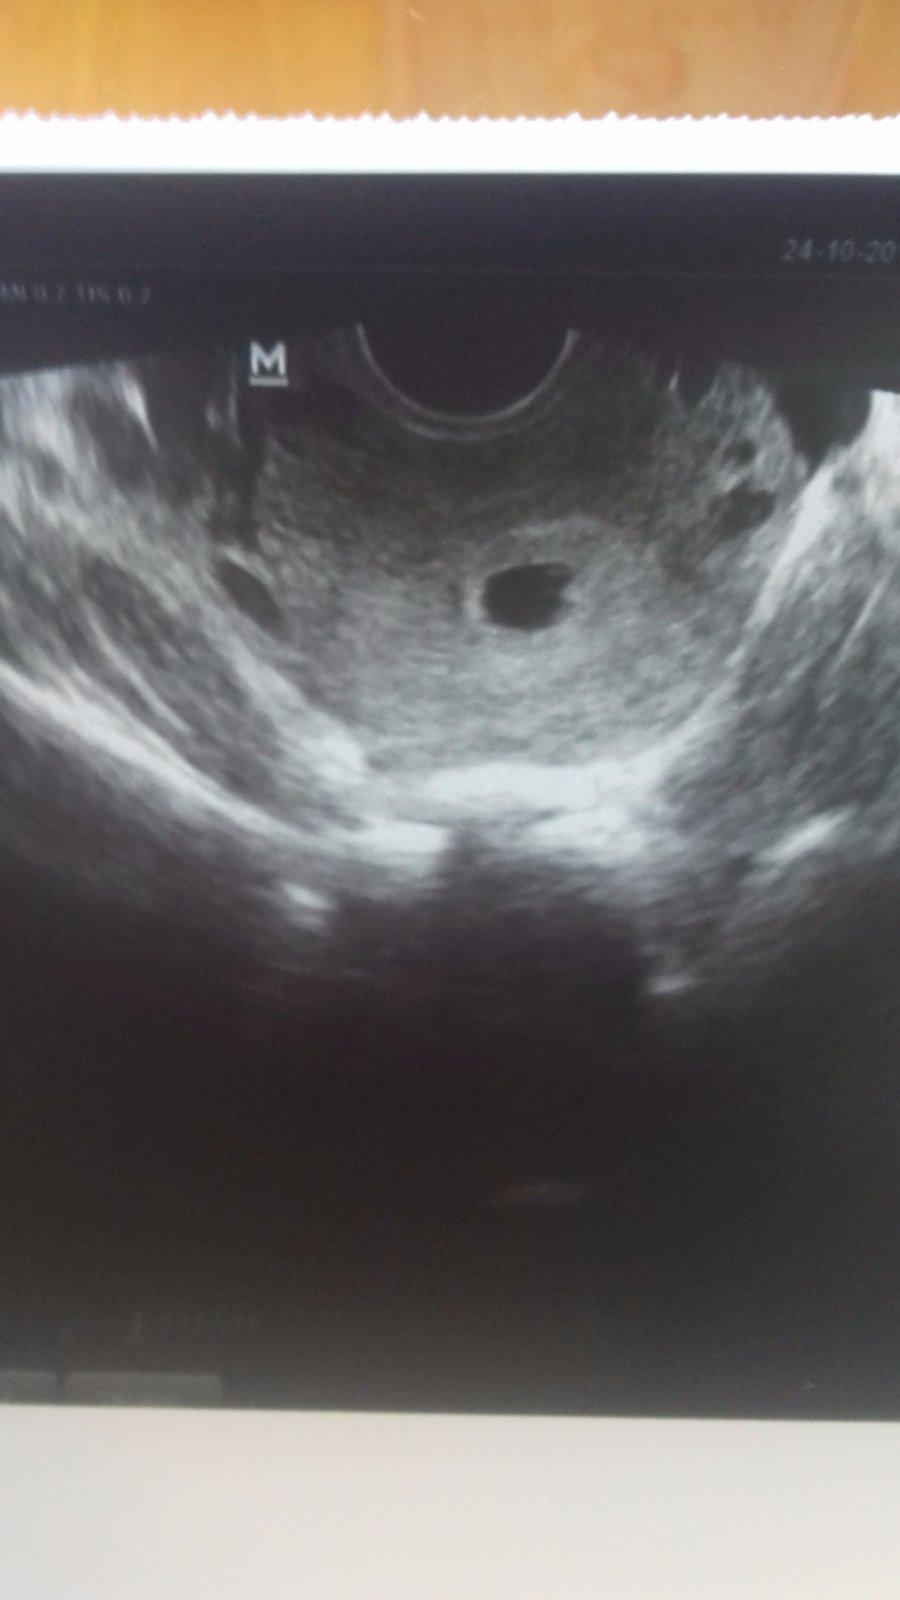

Ja uz dnes takto baby ☺